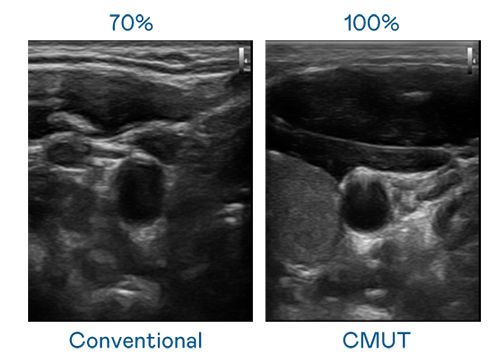

申博太陽城運(yùn)用 TFT 陣列 (Array) 制程延伸尖端感測技術(shù) ,開發(fā)出多種感測元件的產(chǎn)品。高解析度、品質(zhì)穩(wěn)定且可量產(chǎn)的 CMUT 元件,可制作高解析度超音波探頭、貼片型探頭 ,對病患實(shí)施精準(zhǔn)檢測與長時(shí)間生理監(jiān)測 。為滿足 X光設(shè)備輕量化、可移動(dòng) ,甚至需針對待測物進(jìn)行外觀客制化的新需求 ,申博太陽城結(jié)合非晶矽 (a-Si) 制程與新的封裝技術(shù),實(shí)現(xiàn)可撓曲、具優(yōu)異 TFT 遷移率 (mobility) 的柔性 X光感測器。目前也已提供完整玻璃和曲面型 X光感測器檢測解決方案 。